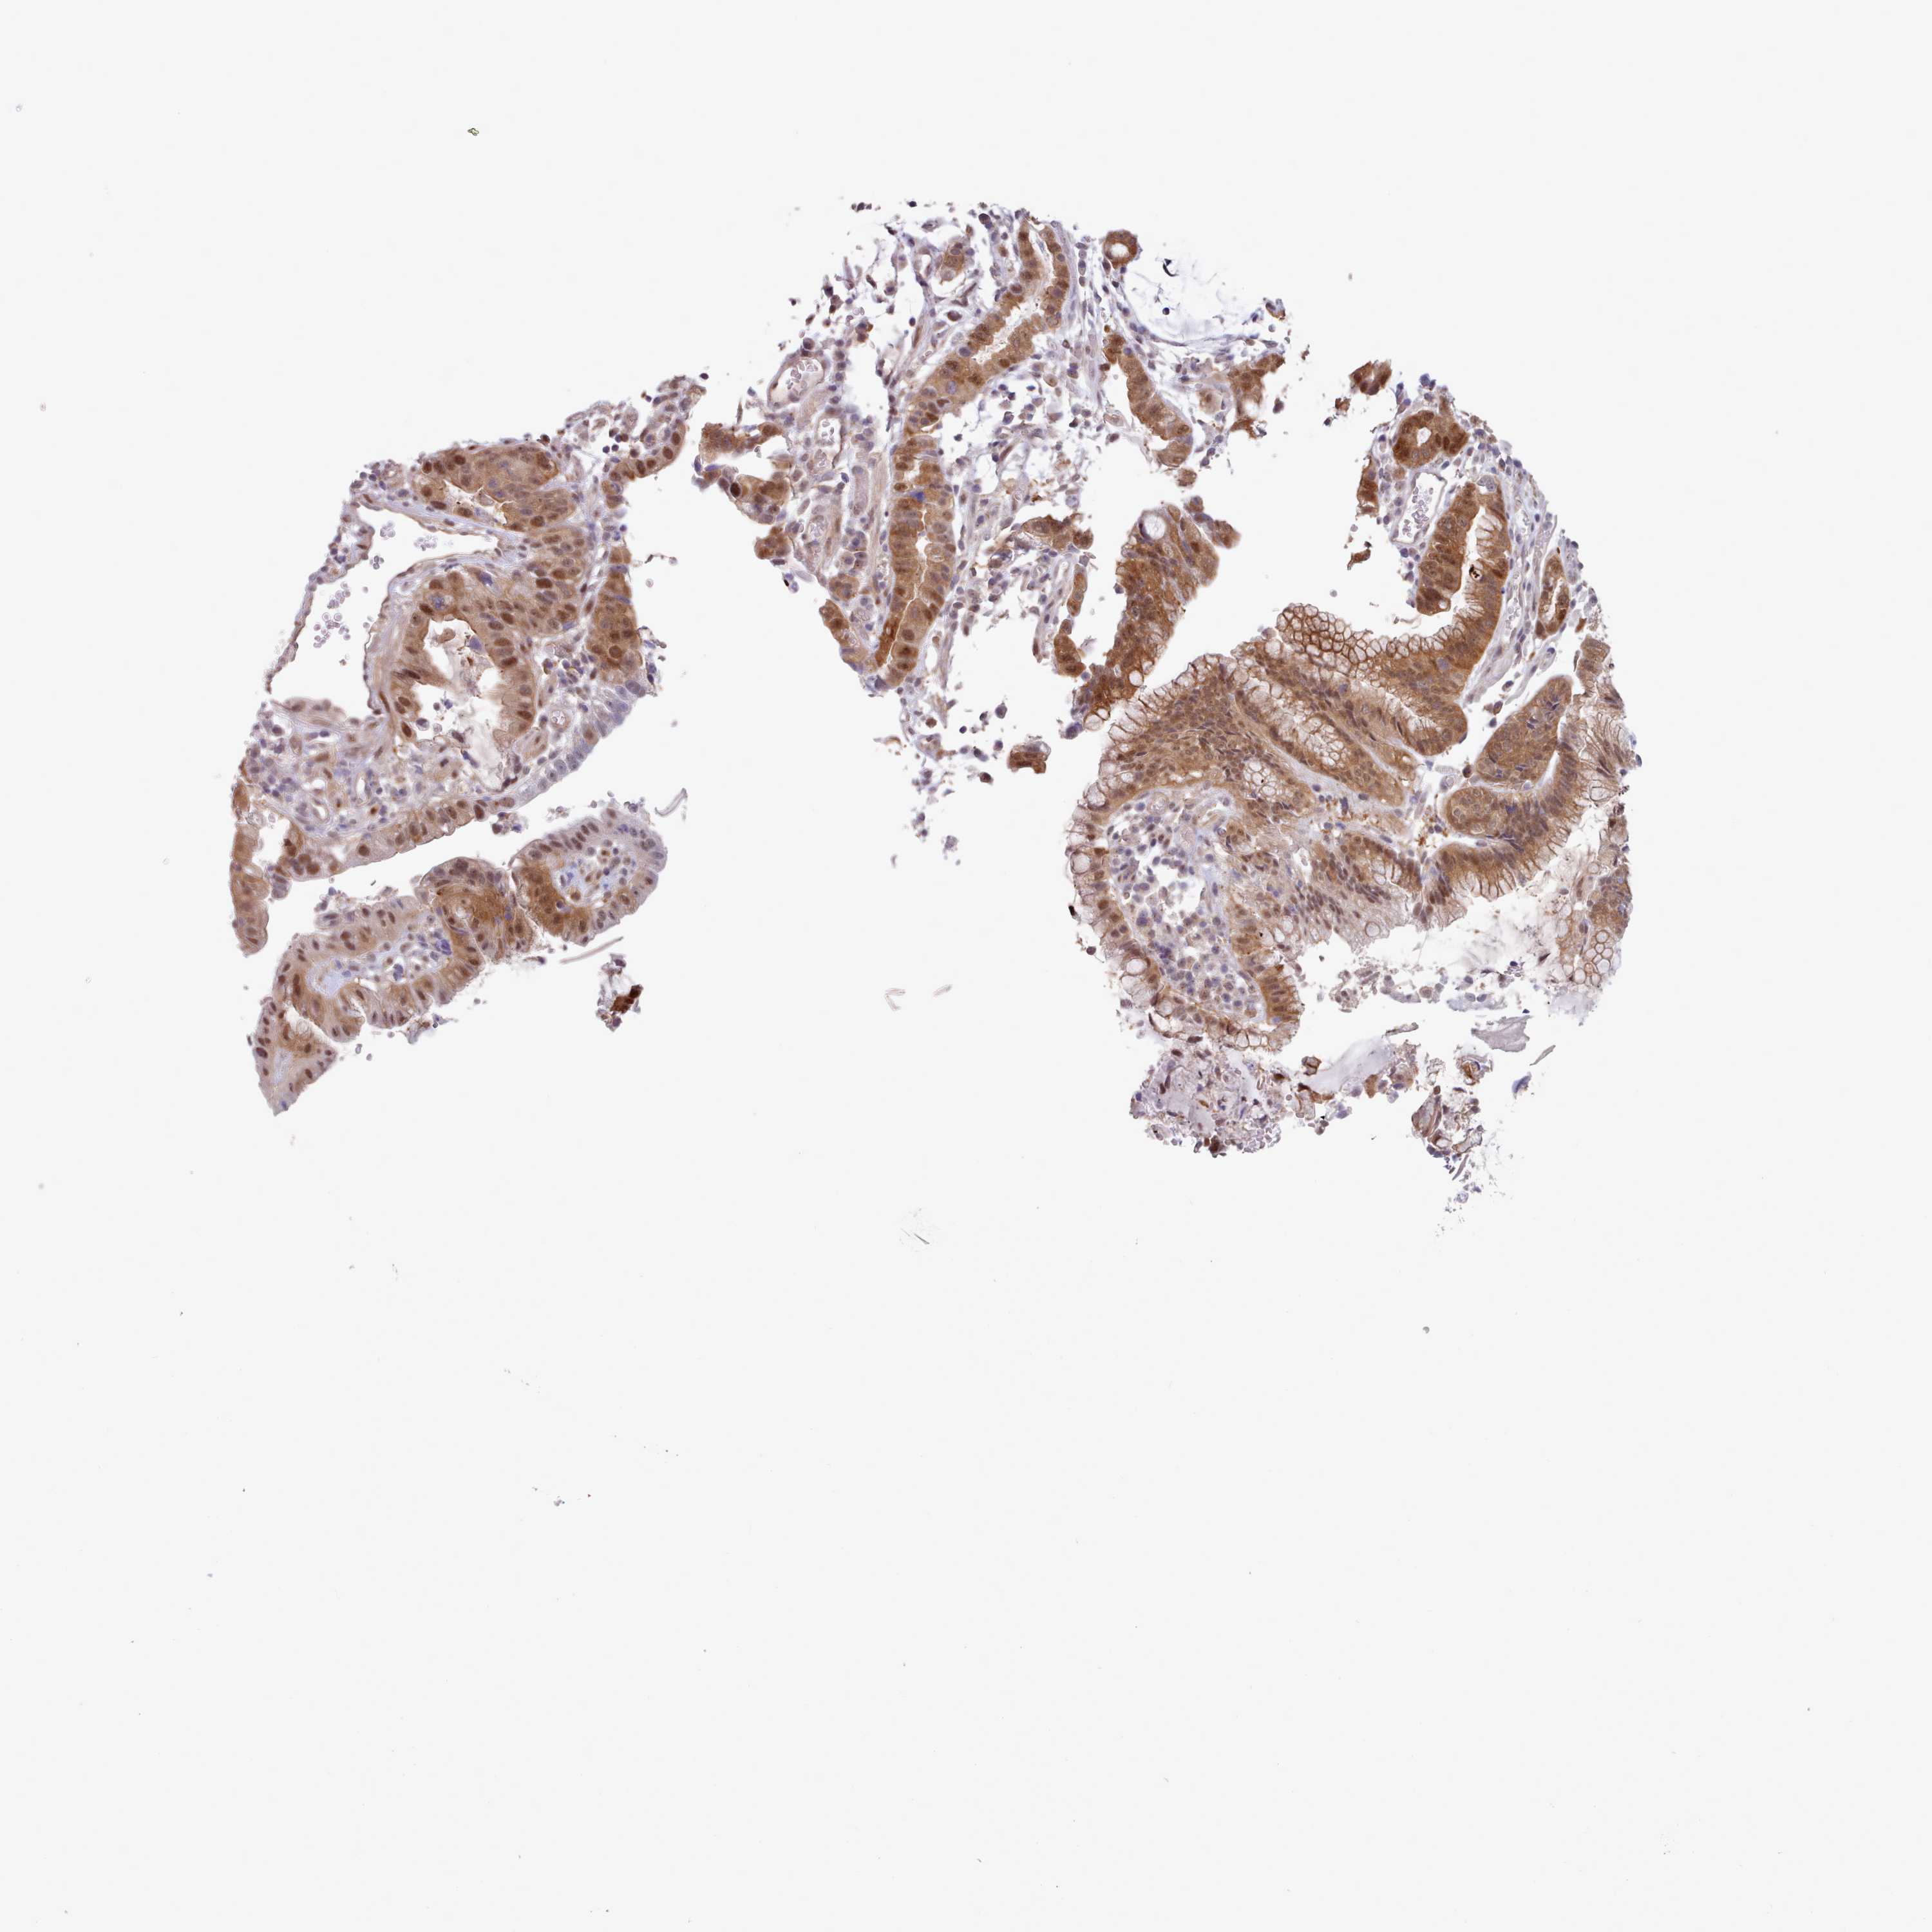

STOMACH CANCER - Protein expressioni

A mouse-over function shows sample information and annotation data. Click on an image to view it in a full screen mode. Samples can be filtered based on level of antibody staining by selecting one or several of the following categories: high, medium, low and not detected. The assay and annotation is described here.

Note that samples used for immunohistochemistry by the Human Protein Atlas do not correspond to samples in the TCGA dataset.

Antibody stainingi

Antibody staining in the annotated cell types in the current human tissue is reported as not detected, low, medium, or high, based on conventional immunohistochemistry profiling in selected tissues. This score is based on the combination of the staining intensity and fraction of stained cells.

Each image is clickable and will lead to virtual microscopy that enables deeper exploration of all samples and also displays staining intensity scores, fraction scores and subcellular localization as well as patient and tissue information for each sample.

Antibody HPA041008

Antibody HPA041307

Staining

High

Medium

Low

Not detected

Intensity

Strong

Moderate

Weak

Negative

Quantity

>75%

75%-25%

<25%

None

Location

Nuclear

Cytoplasmic/membranous

Cytoplasmic/membranous,nuclear

Adenocarcinoma, NOS